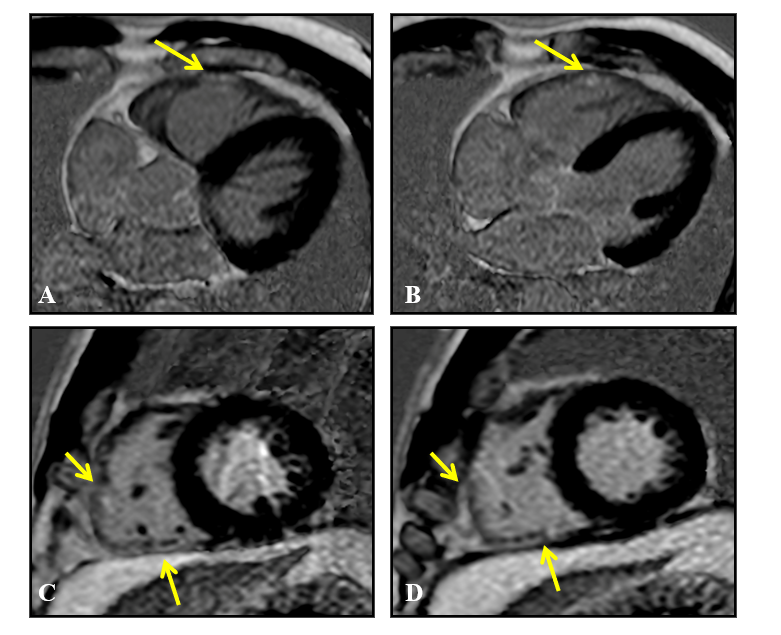

Figure 3 Magnetic resonance imaging, late gadolinium enhancement sequences, 4 chambers (A and B) and short axis (C and D) showing pathological late enhancement areas in the myocardium of the inferior and lateral segments of the right ventricular free wall (arrows), without associated left ventricular involvement.

Figure 6 Cardiac magnetic resonance imaging, late gadolinium enhancement sequences, 4 chambers (A and B) and short axis (C and D), showing areas of pathological late enhancement in the myocardium of the inferior-lateral segment of the right ventricular free wall (arrows), without associated left ventricular involvement.